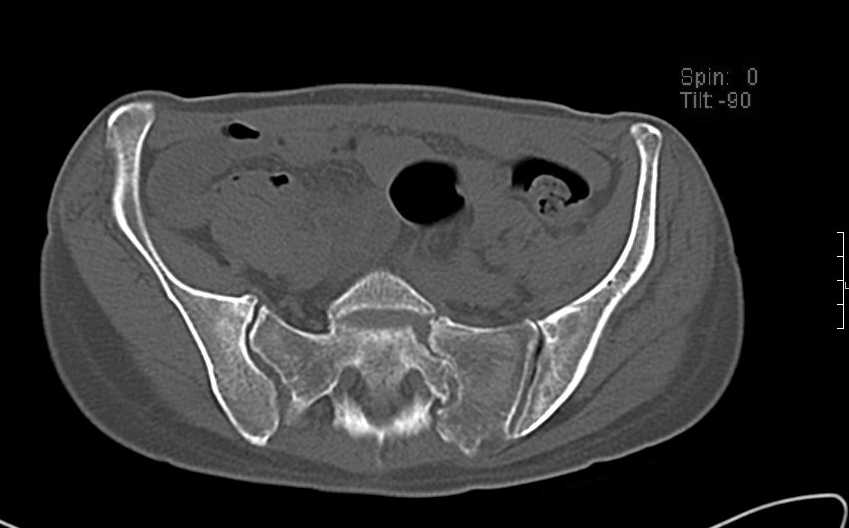

Больная 43 года (промышленный альпинист), 28.07.08 в результате падения с 5 этажа получила политравму: Перелом свода и основания черепа. Вертикально-нестабильное повреждение таза, осложнённое разрывом мочевого пузыря. Чрезвертельный перелом левого бедра. Перелом правой таранной кости, переломовывих правой кубовидной кости. Тупая травма живота, разрыв печени, ушиб почек. Забрюшинная гематома. В день травмы - лапаротомия, ушивание ран печени. Разрыв мочевого пузыря не диагностирован. Течение болезни осложнилось развитием мочевого затёка и обширной пред- и забрюшинной флегмоны, сформировался свищ мочевого пузыря. 19.8.2008 вскрытие, дренировние флегмоны, ревизия мочевого пузыря, обтурация мочевого свища (свищ закрылся в октябре), 1.10.2008 некрэктомия, пластика по Шеде-Лидскому правой кубовидной кости. По результатам КТ диагностирован рак правой почки (диагностическая находка), 8.10.2008 нефрэктомия справа. Переломы велись консервативно. Имеется вертикальное смещение левой половины таза с выраженным отведением крыла (клинически подвижности нет), несросшийся низкий двухколонный перелом левой вертлужной впадины с потерей конгруэнтности, укорочение около5 см, застарелый разрыв лонного сочленения, неправильно сросшиеся переломы обеих ветвей правой лонной кости с укорочением, патологическая подвижность лоно-седалищного фрагмента слева. Правая нижняя конечность неопорна, несмотря на то, что лежа прямую ногу поднимает, ходит на левой ноге (ортопедическая обувь) с костылями, справа тазобедренный ортез. Седалищные нервы работают.Урологи отпустили больную на 6 мес.

Извиняюсь, ошибся : опорная нога у больной правая. Левая нога неопорная, т.к. сращения на уровне бедра и вертлужной впадины нет.